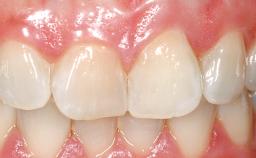

Late Placement of an Implant in a Maxillary Left Central Incisor Site

On examination, the patient had a low lip line and only displayed the coronal half of the anterior teeth when smiling.